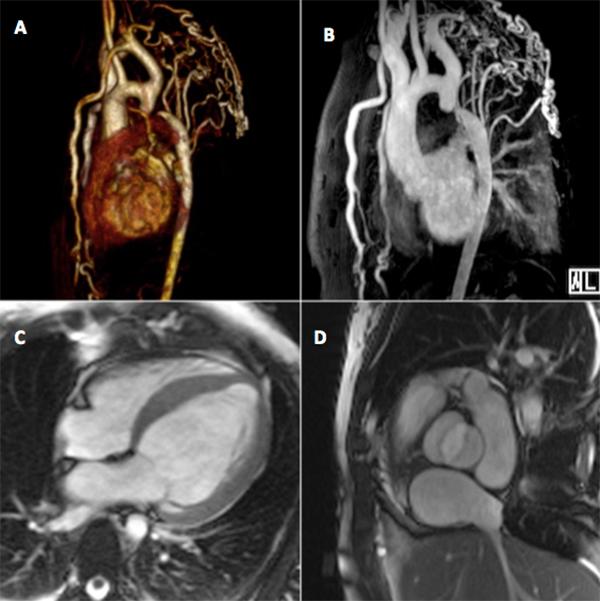

Interrupted aortic arch (IAA) is a rare congenital abnormality with only a few cases reported in adults. It is defined as complete loss of continuity between the ascending and descending portions of the aorta, and is usually associated with other cardiac defects. The diagnosis in adults should be suspected in the presence of refractory hypertension, a careful physical examination being crucial to early diagnosis. Magnetic resonance angiography (MRA) techniques can accurately characterize cardiovascular anatomy, and also provide information regarding heart chamber and valve function.

Although rare, interrupted aortic arch (IAA) must be considered in the differential diagnosis of adults with refractory hypertension. A careful physical examination, with evaluation of femoral pulses and blood pressure in the four limbs, is essential for the diagnosis and for ensuring that the correct diagnosis is made promptly.This case highlights the value of magnetic resonance angiography (MRA) in radiation-free non-invasive evaluation of adults with congenital aortic abnormalities, as it may provide clinically important haemodynamic information.Only a few cases have been reported in adults. We present an unusual case in which the diagnosis was not made until adulthood.